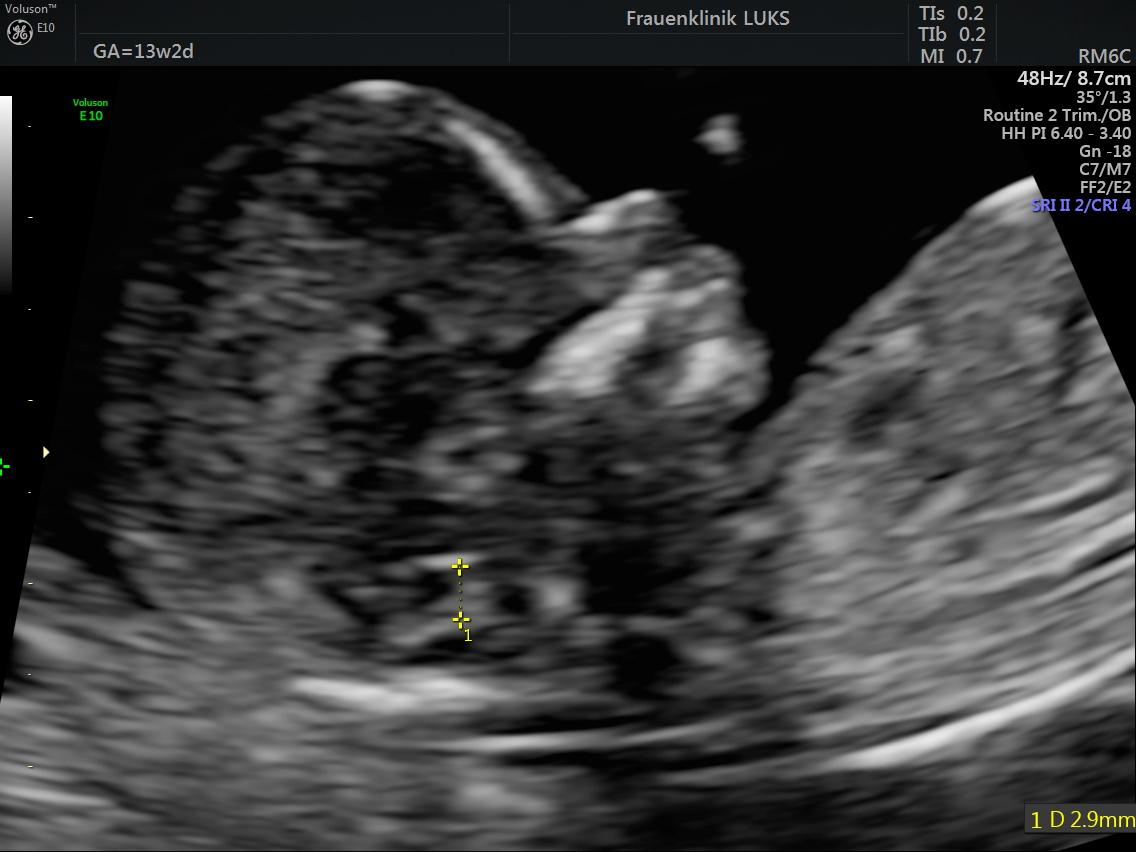

Chen FC et al. Detection of Spina Bifida by First Trimester Screening – Results of the Prospective Multicenter Berlin IT-Study, Ultraschall in Med 2017; 38: 151–157

IT Beispielbild

IT / CM / BS Anleitung Messung

IT / CM / BS Tabelle Normwerte